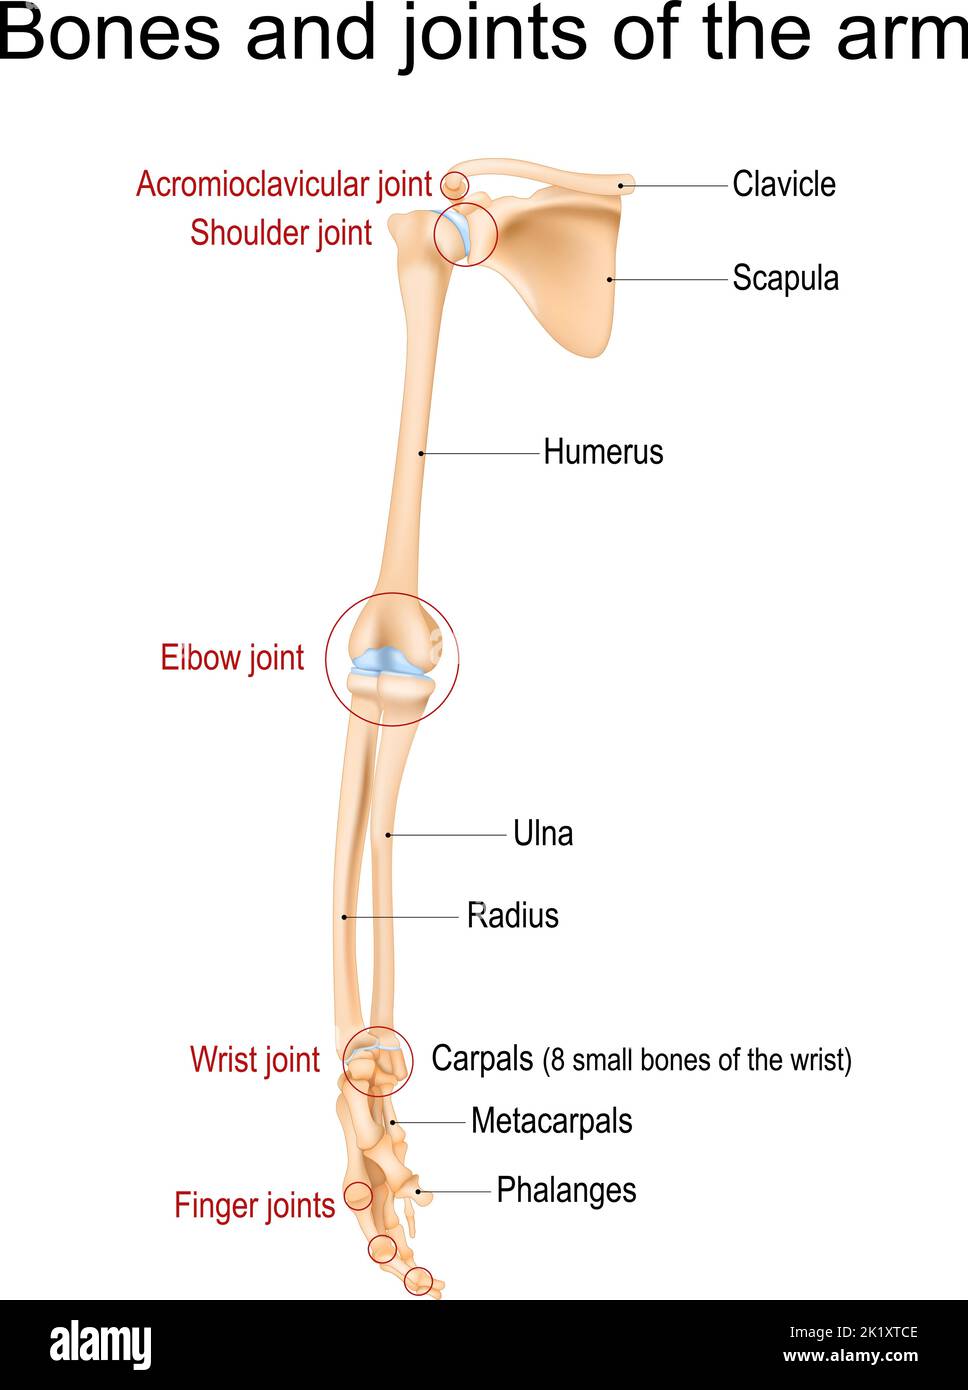

RF2K1XTCE–Anatomie des menschlichen Arms. Knochen und Gelenke von Arm, Unterarm und Hand. Vorderansicht des oberen Gliedes des Skeletts. Vektorgrafik